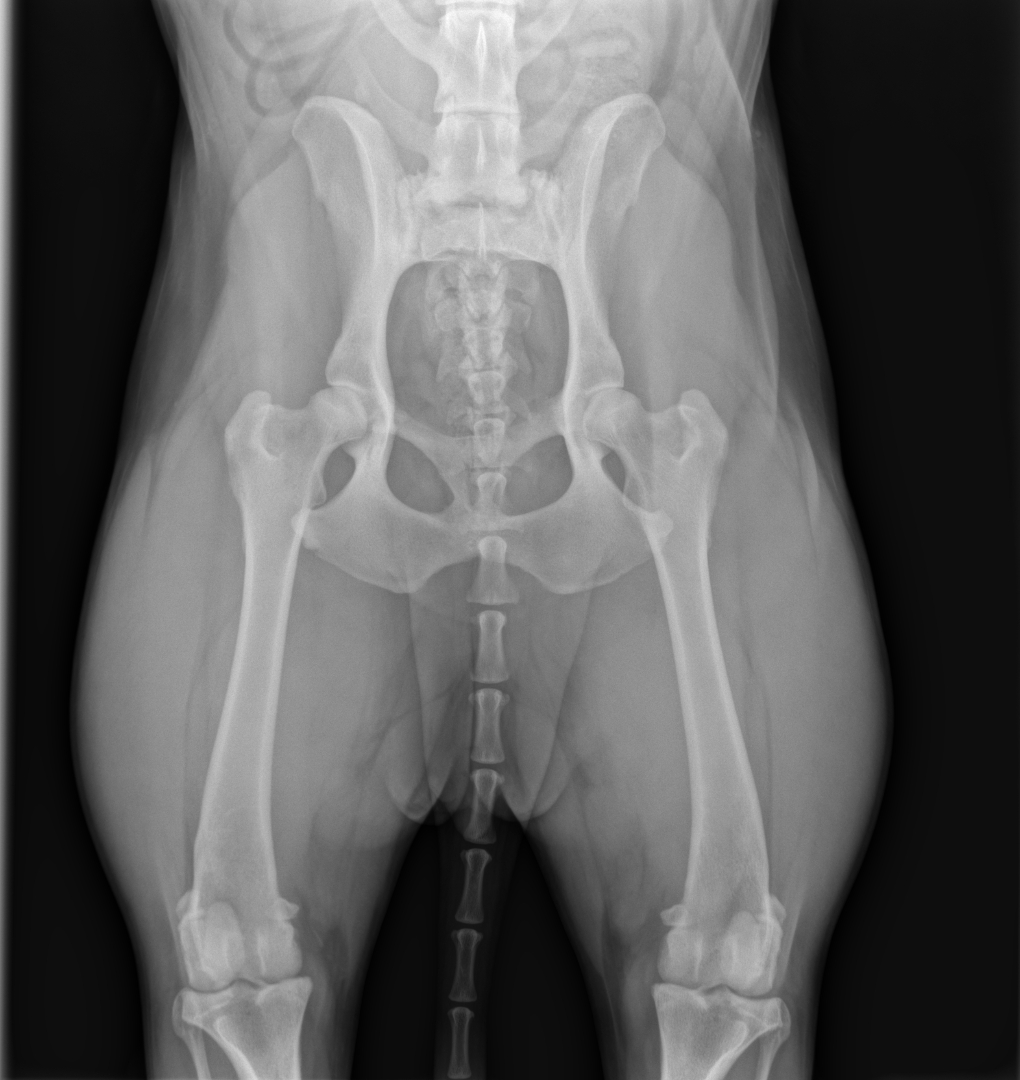

Boiterie des 4 membres

2025-11-07 15:06:20

放射学